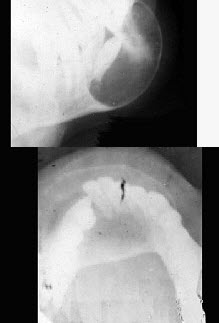

女性,40岁,下颌颏部隆起,X线检查如图所示,请选择最可能诊断()。

A、造釉细胞瘤

B、骨软骨瘤

C、含牙囊肿

D、骨巨细胞瘤

E、动脉瘤样骨囊肿

C